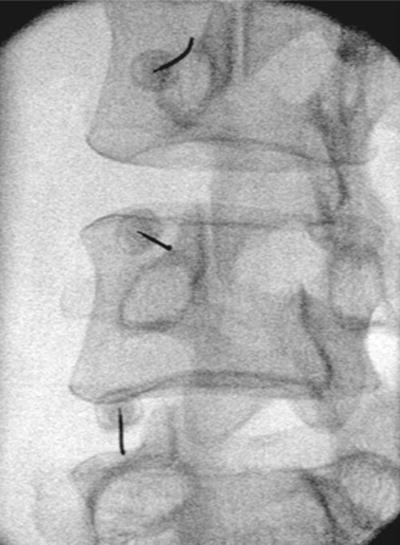

Πρόκειται για μια ελάχιστα επεμβατική πράξη, όπου μια ειδική βελόνα με ενσωματωμένο ηλεκτρόδιο εισάγεται στο σπονδυλικό τρήμα στο επίπεδο του ραχιαίου γαγγλίου της οπίσθιας ρίζας. με χρήση παλμικής ραδιοσυχνότητας γίνεται η διέγερση του γαγγλίου, με στόχο την τροποποίηση της μεταφοράς και αντίληψης των επώδυνων μηνυμάτων.